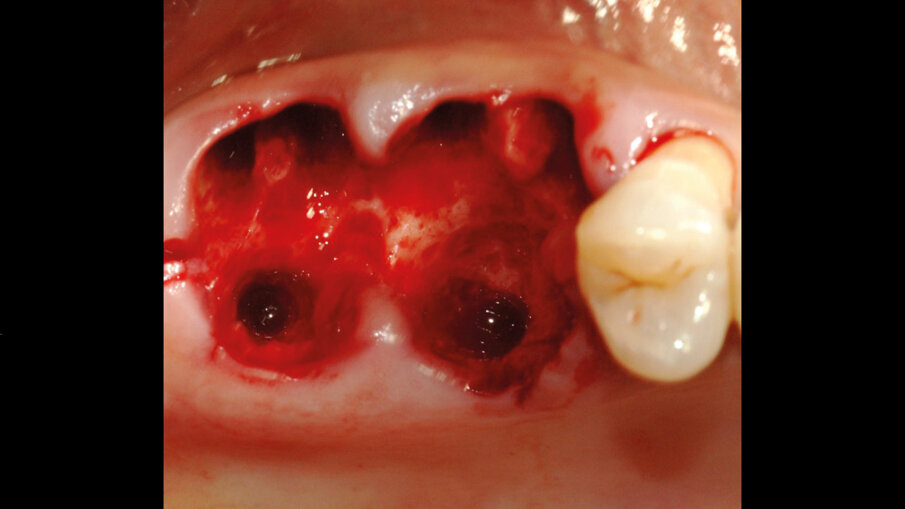

Il giorno prima dell’intervento, la paziente veniva sottoposta a terapia antibiotica con Amoxicillina e Acido Clavulanico compresse da 1 gr ogni 12 ore. Il giorno dell’intervento veniva eseguita la profilassi antibiotica 1 ora prima dell’inizio con 875/125 mg di Amoxicillina+ Acido Clavulanico e veniva praticata l’anestesia locale con Articaina + adrenalina 1:100.000. Quindi si procedeva all’estrazione dei due elementi compromessi (Fig. 2) e si provvedeva alla preparazione del sito implantare all’interno della radice palatina; gli autori considerano questa la sede di elezione ove la zona del setto inter-radicolare non fosse idonea ad accogliere l’impianto. Una volta preparati i tunnel implantari nei siti 26 e 27, venivano inseriti due impianti 4.3 x 10 mm (IDI evolution Tiger) (Fig. 3). La stabilità implantare veniva misurata mediante il rapporto e lo scambio di energia tra la superficie di contatto ossea e l’impianto ottenendo un valore oggettivo (Newton/cm) che rappresenta la stabilità implantare (TMM3 IDI evolution) (Fig. 4).

Fig. 2 - Estrazione dei due elementi compromessi.